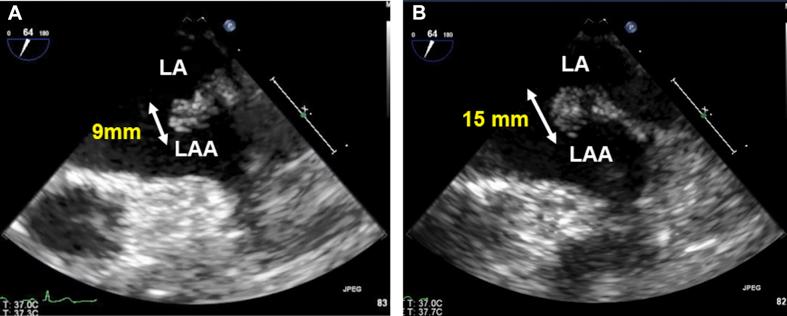

A 70-year-old woman presented with aphasia caused by acute infarction in the left middle cerebral artery. Cardiac investigation revealed progressively increasing mobile mass in the left atrial appendage over 2 months (from 9 to 15 mm). Decision was made to proceed with mass resection, and pathological evaluation confirmed Masson tumor. ().